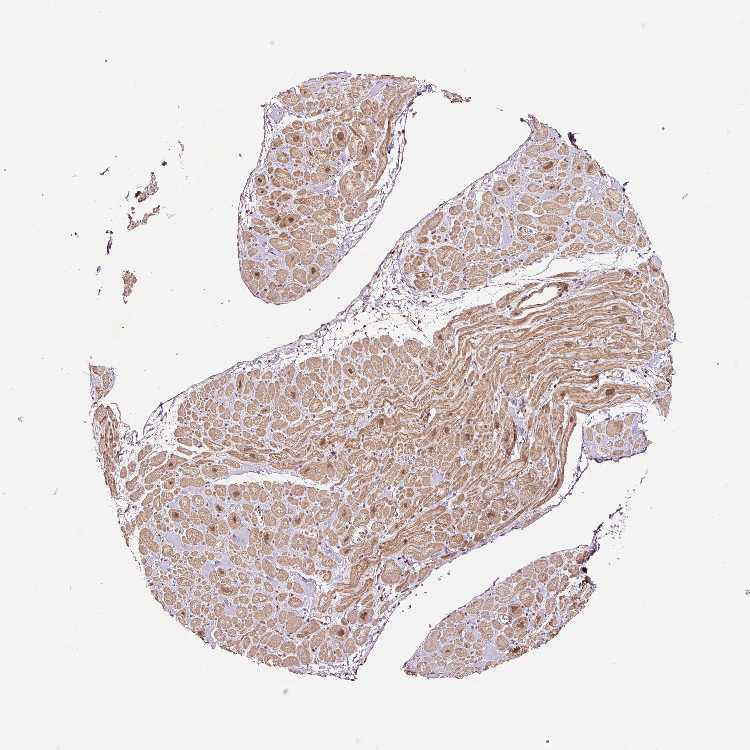

TISSUE PRIMARY DATA HEART MUSCLE Show tissue menu

Heart muscle

Heart

HEART MUSCLE - Expression summary

Protein expression

Heart musclei

On the top, protein expression in current human tissue, based on all annotated cell types, is reported with the units not detected (n), low (l), medium (m) and high (h). Underneath, protein expression in each annotated cell type are reported using the same units.

Protein expression data is based on knowledge-based annotation. For genes where more than one antibody has been used, a collective score is set.

If knowledge-based annotation could not be performed for a gene, no data is displayed here. View antibody staining data further down this page.

Cardiomyocytes: Low

HEART MUSCLE - Antibody stainingi

Antibody staining in the annotated cell types in the current human tissue is reported as not detected, low, medium, or high, based on conventional immunohistochemistry profiling in selected tissues. This score is based on the combination of the staining intensity and fraction of stained cells.

Each image is clickable and will lead to virtual microscopy that enables deeper exploration of all samples and also displays staining intensity scores, fraction scores and subcellular localization as well as patient and tissue information for each sample.

Antibody HPA049123Antibody HPA058507Antibody CAB004557

Cardiomyocytes HighNot detectedNot detected